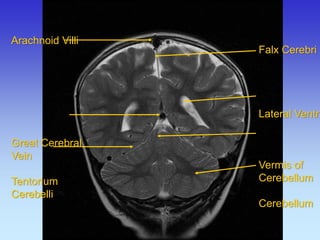

Arachnoid Villi

Great Cerebral

Vein

Tentorium

Cerebelli

Falx Cerebri Lateral Ventricle Vermis of Cerebellum Cerebellum